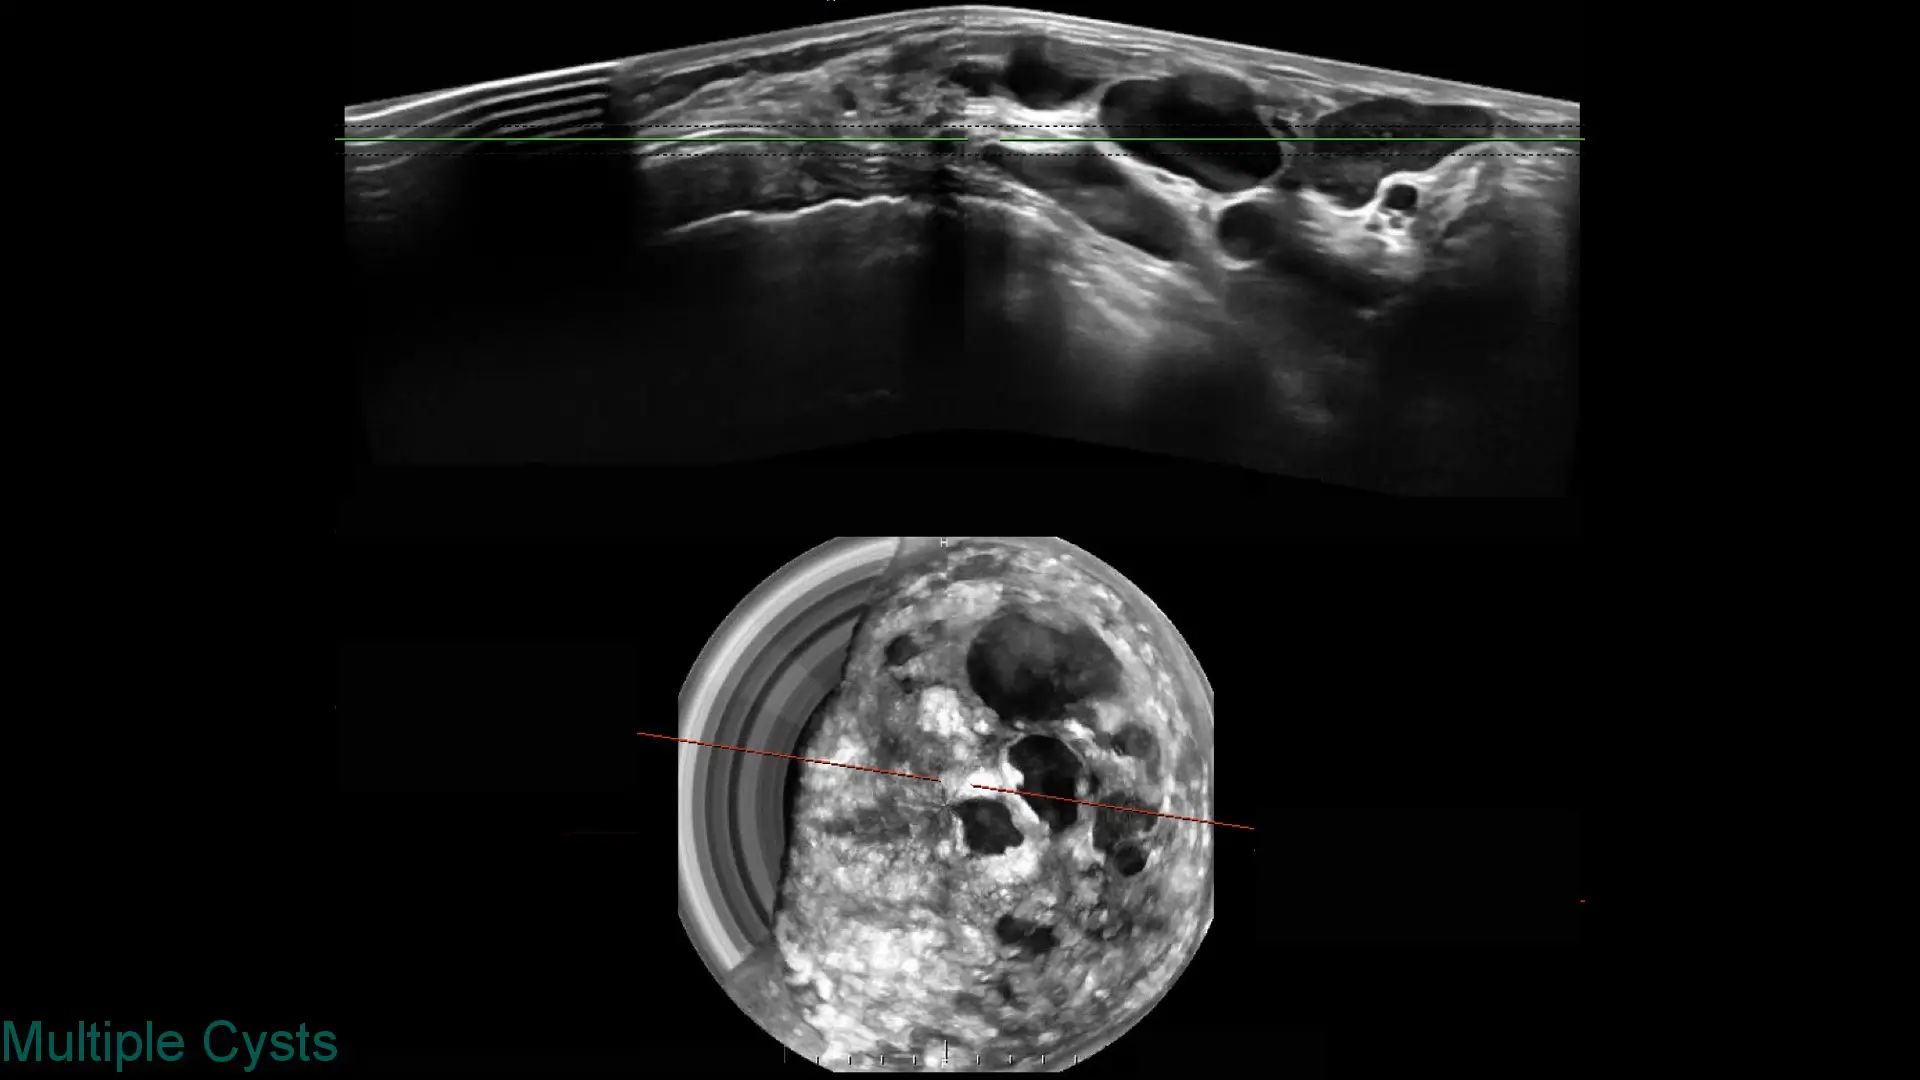

Explore clinical breast ultrasound images captured with SOFIA, showcasing various tissue types and conditions with exceptional clarity.